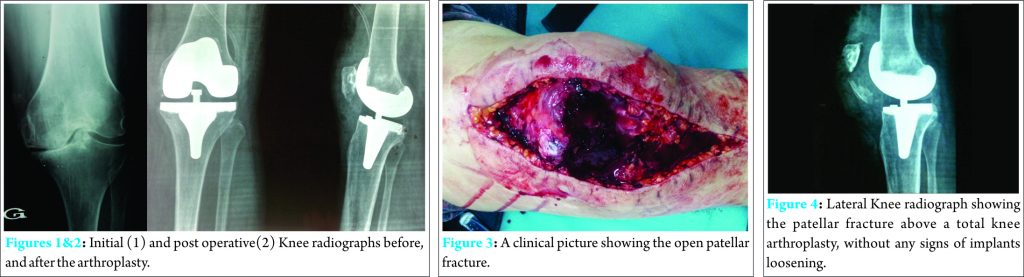

A 56-year-old female underwent a cemented postero-stabilized condylar TKA with fixed tibial plateau through an antero-medial approach, in our department. She had severe osteo-arthritis of the left knee with a major stiffness (irreducible flexum at 25°). (Fig. 1, 2) Initial (1) and post operative(2) Knee radiographs before, and after the arthroplasty.Three weeks later, the patient tripped and fell off with all her standing height striking the anterior aspect of the left knee with hyper flexion. She was taken to the emergency room with left knee pain and a large skin wound. Physical examination showed a large, deep and longitudinal wound measuring 15 cm in length due to a total breakdown of the suture line (the antero-medial approach performed during the TKA) (Fig. 3, 4).

Fig 3. A clinical picture showing the open patellar fracture

Fig 4. Lateral Knee radiograph showing the patellar fracture above a total knee arthroplasty, without any signs of implants loosening.

The knee radiographs showed a short oblique fracture at the inferior pole of the patella without any loosening of the implants or dislocation of the knee: this fracture is classified as type I according to Ortigueraet D.J. Berry classification [8][9] (a stable implant without disruption of the extensor mechanism).